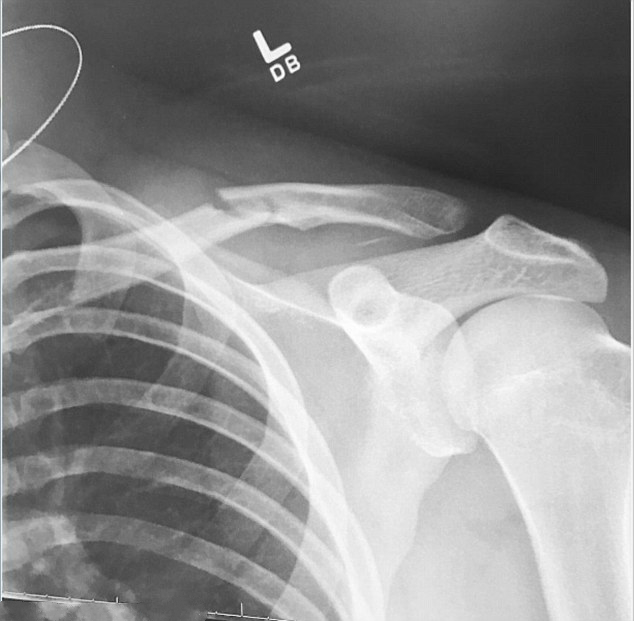

在视频上传后4小时内,点击量已高达40万,标题是“最后一下摔折了锁骨”。数小时后他分享了自己的X光片,展现锁骨处的裂痕,在接下来的行程中他都没法浪了。